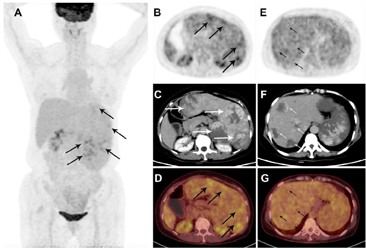

②18F-FDG PET/CT:脾脏明显增大,约23.1 cm×12.4 cm×24.5 cm,密度弥漫性减低,平均CT值约39 Hu,其内见多发条片状更低密度影,CT值约31 Hu,脾脏18F-FDG代谢不均匀性轻度增高,SUVmax=5.4;肝内多发类圆形低密度影,形态规则,边缘光整,最大者直径4.4 cm,密度均匀,平均CT值约42 Hu,病灶18F-FDG摄取均匀,与肝本底无差异,SUVmax=3.3(图1);诊断意见:巨脾伴18F-FDG代谢不均匀轻度增高,倾向恶性病变(原发);肝内多发低密度灶未见18F-FDG代谢异常,倾向良性病变(血管瘤)。

PSA是一种罕见的血管源性恶性肿瘤,预后极差。血管肉瘤在增强CT的影像学表现与良性的血管瘤具有一定相似性,鉴别诊断难度较大[2]。既往病例报道,各部位原发的血管肉瘤均有不同程度18F-FDG代谢增高[3,4],而血管瘤很少出现代谢增高的情况[5]。因此18F-FDG PET/CT在鉴别血管肉瘤与血管瘤方面具有一些作用。本例术前增强CT的异常强化特点提示肝脾病灶均为血管来源,但良恶性却较难鉴别,故行18F-FDG PET/CT检查以获得病灶代谢信息。脾脏代谢增高,提示为恶性病变,术后病理亦证实了这一点,而肝脏病灶的良恶性鉴别存在挑战性。根据PSA的转移特性,肝多发转移是需要考虑的,术后随访亦证实其为转移瘤,但肝脏病灶却无代谢异常,这种与PSA同时存在的、18F-FDG代谢与肝脏本底相同的肝转移灶,易与肝血管瘤混淆,是罕见且有趣的病例。与本病例不同,Cao和Krol各报道了1例PSA伴肝转移,肝转移灶均18F-FDG代谢减低,这可能与肿瘤内部出血和坏死有关[1,6]。而Shimada报道了2例较大的血管瘤,病灶亦因内部坏死、纤维化而代谢减低[2]。因此,18F-FDG PET/CT在血管肉瘤中的价值可能是有限的,因为肝转移灶的代谢似乎没有规律可言。双时相18F-FDG PET/CT可能会提供更多的信息[7],需要进一步研究。

由于PSA罕见,我们对其转移灶的代谢特点缺乏深刻的认识。遗憾的是,本例术前18F-FDG PET/CT检查未行肝脏双时相显像,术后亦未复查18F-FDG PET/CT,我们无法得知双时相显像是否对此类肝转移瘤具有诊断价值,以及肝转移瘤在进展过程中的代谢变化,这是本例报道的不足之处。本例PSA伴肝转移的18F-FDG PET/CT表现与以往报道的病例均不同,提示对PSA患者进行18F-FDG PET/CT评估时,对于肝脏可疑病灶,即使代谢正常,亦不能排除转移的可能性。